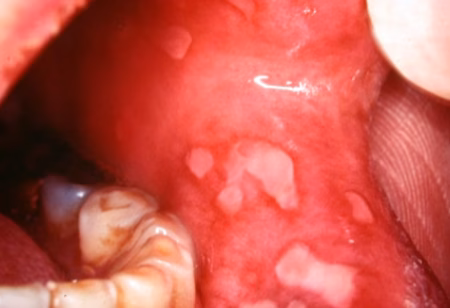

1. Lichen Planus

One of the most common mucocutaneous diseases.

What patients may see:

- White, lacy lines on the cheeks

- White patches on gums or tongue

- Red, thin, or irritated areas

- Occasional painful ulcers